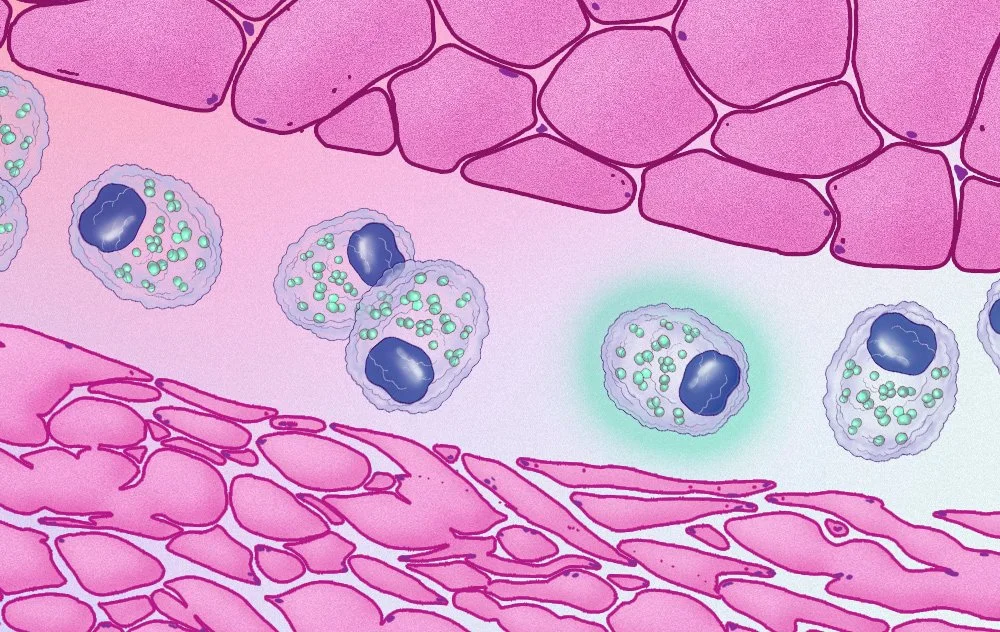

We work with biotech companies to visualize their state-of-the-art technology - from cancer diagnostics to neuroscience technology to patient simulation technology and more.

We are no strangers to the life sciences. Our medical animations animations can show how molecules interact in the body, how surgical procedures are performed, or how a new drug works at the cellular level. These visual aids help healthcare professionals, researchers, and patients understand complex medical concepts and procedures more easily.

We specialize in a wide variety of medical visual communications. Take a closer look:

Medical Illustration